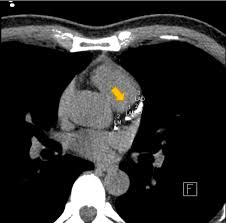

3. 진단 방법 – CAC 스코어

- 비침습적 **관상동맥 칼슘 스캔(칼슘 스코어 CT)**로 Agatston score 산출 :contentReference[oaicite:6]{index=6}.

- 0 = 이상 없음, 1–99 = 경증, 100–399 = 중등도, ≥400 = 중증으로 분류되며, 점수가 높을수록 심혈관 위험이 증가합니다 :contentReference[oaicite:7]{index=7}.

- 중등도 이상일 경우 관상동맥 협착 위험이 높으며, 추가 정밀검사 및 적극 치료가 필요합니다 :contentReference[oaicite:8]{index=8}.

- CT 스캔은 빠르고(약 15분), 고해상도이며, 진단·예후 판단에 유용합니다 :contentReference[oaicite:9]{index=9}.